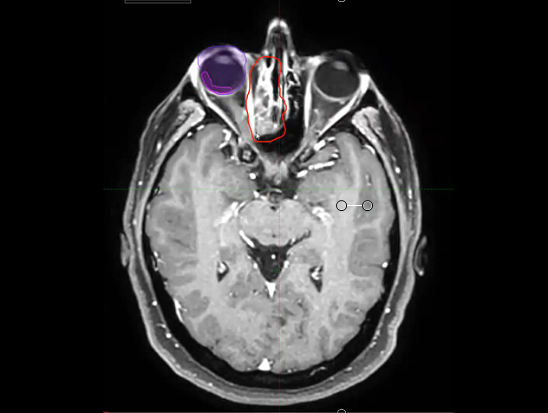

02/27/2023 - Dr. David Sher - Radiation Oncology - US Head & Neck

low risk nodes, hypofractionation, 30 Gy, 40 Gy, sequential boost, simultaneous-integrated boost, SIB, left temple, scab, pembrolizumab adjuvant therapy, occipital node, biopsy, ultrasound, primary site, fraction boost, melanoma, resection, 48 Gy in 20, electrons, superficial, lacrimal gland, IMR...